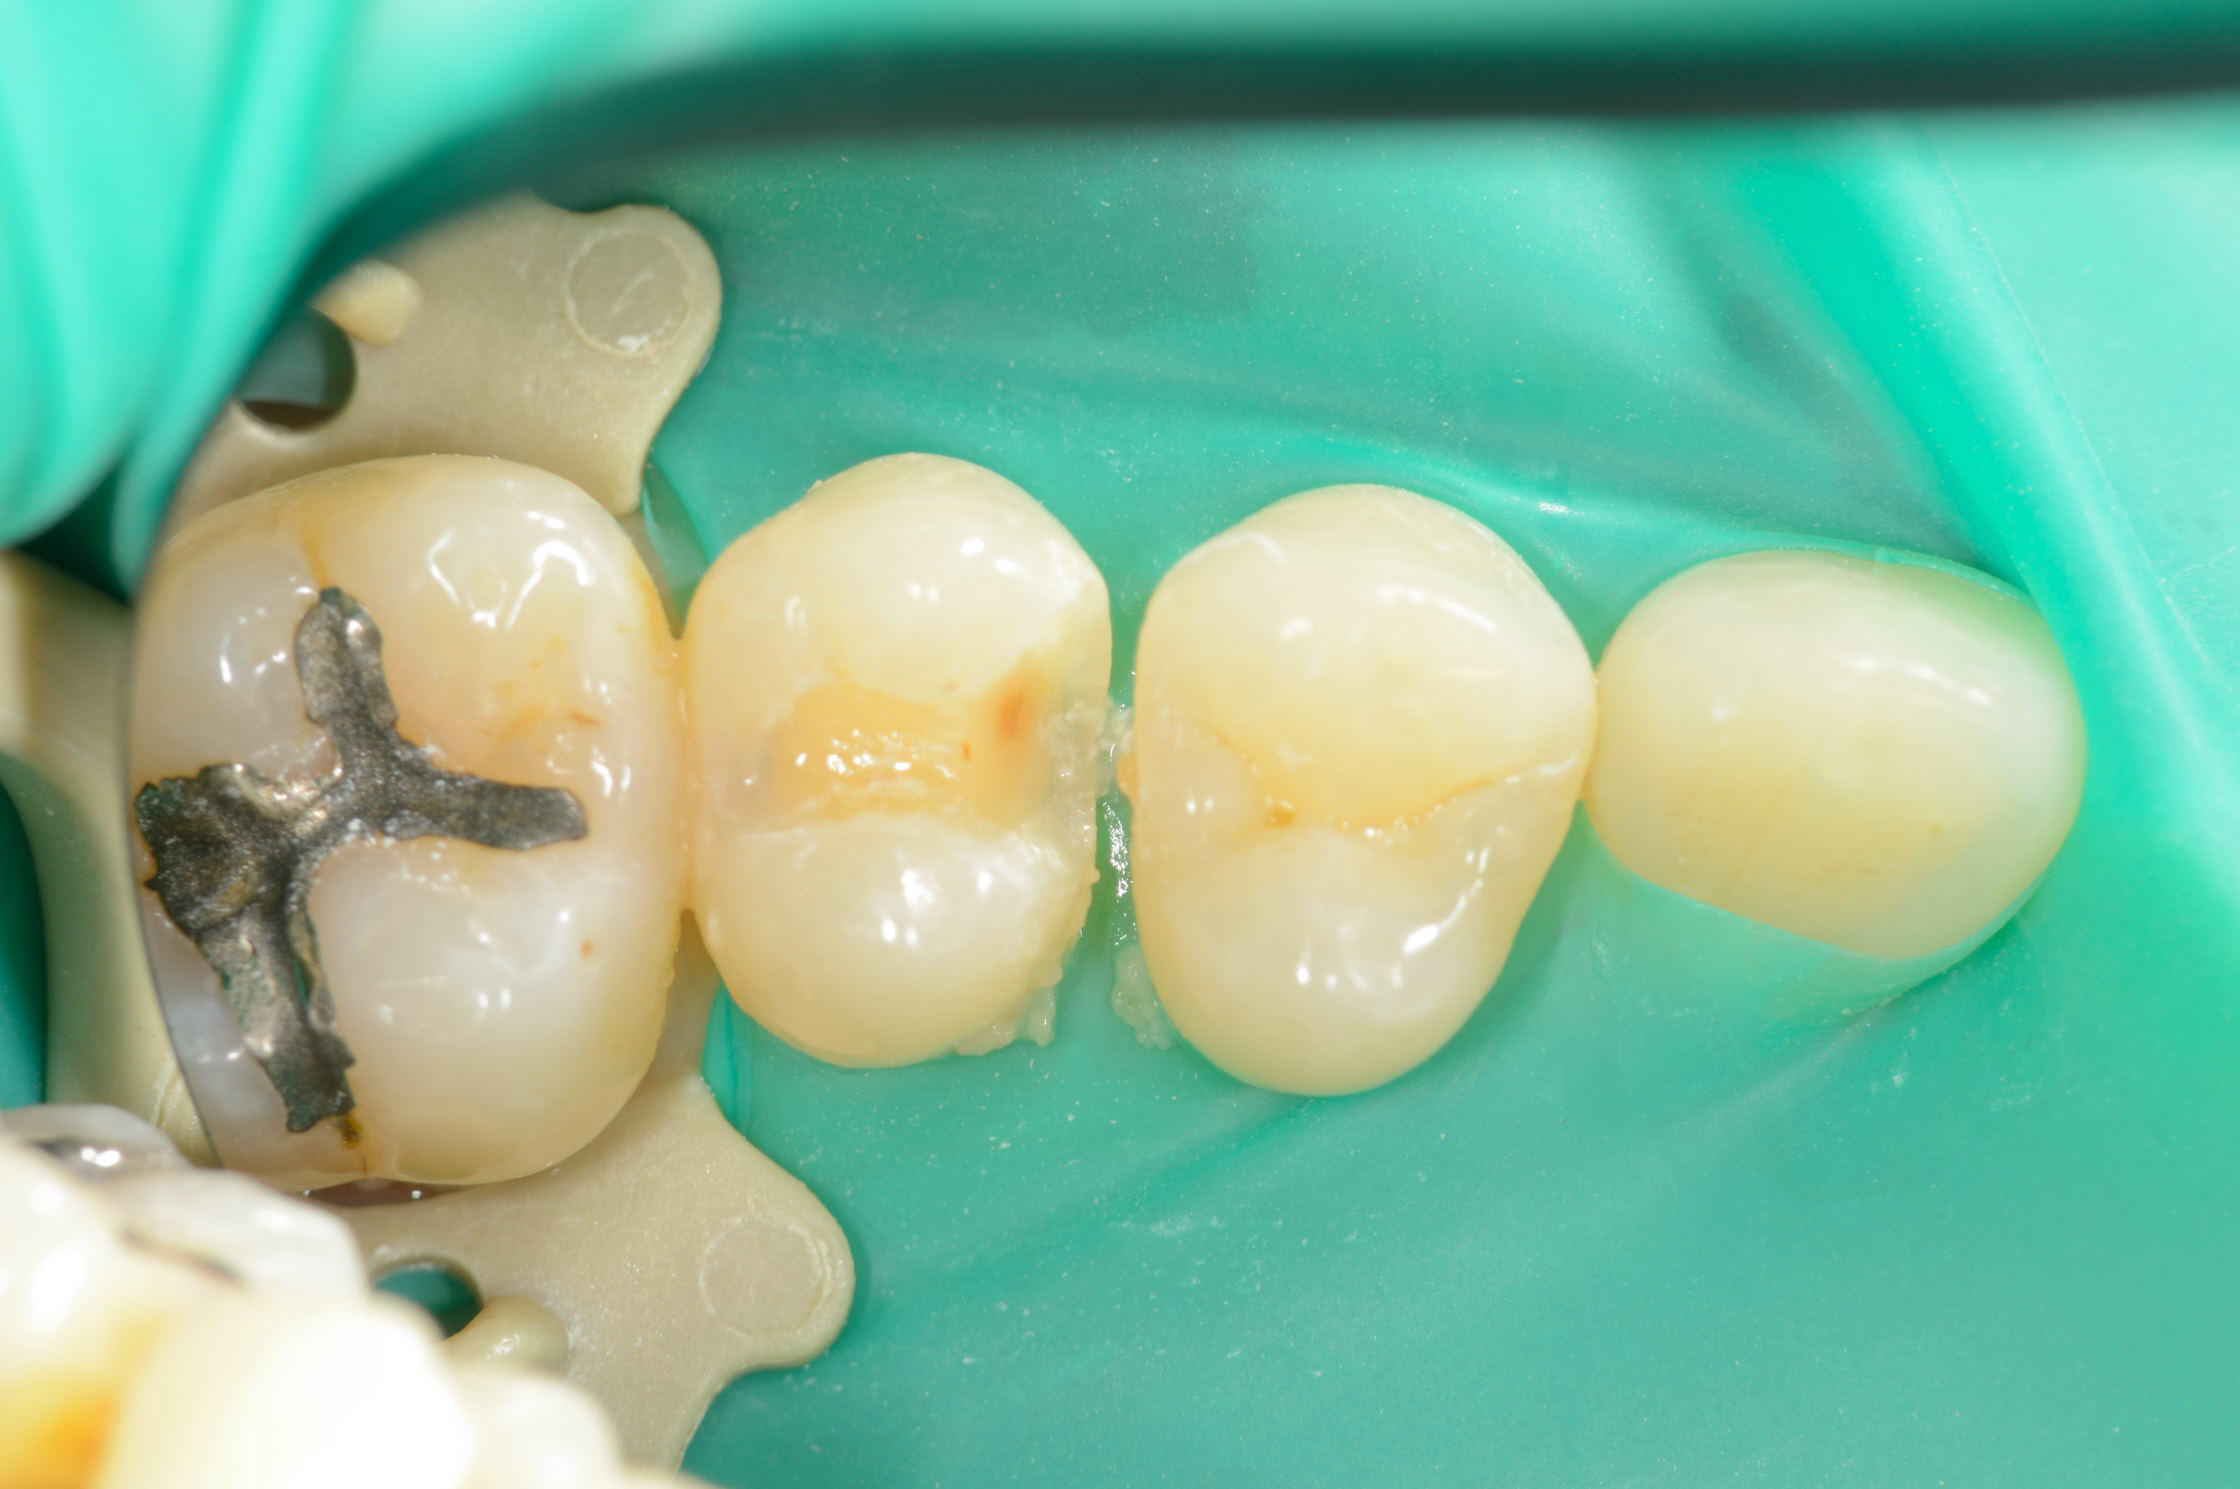

患者さんは3年前にも当院でダイレクトボンディング治療を受けており、今回も同じく「歯をなるべく削らず修復できる治療法」を希望されました。そのため、詰め物の部分のみを最小限に整え、ダイレクトボンディングで修復を行いました。

自然な形態と色調で修復でき、噛んだ時の痛みも解消しました。